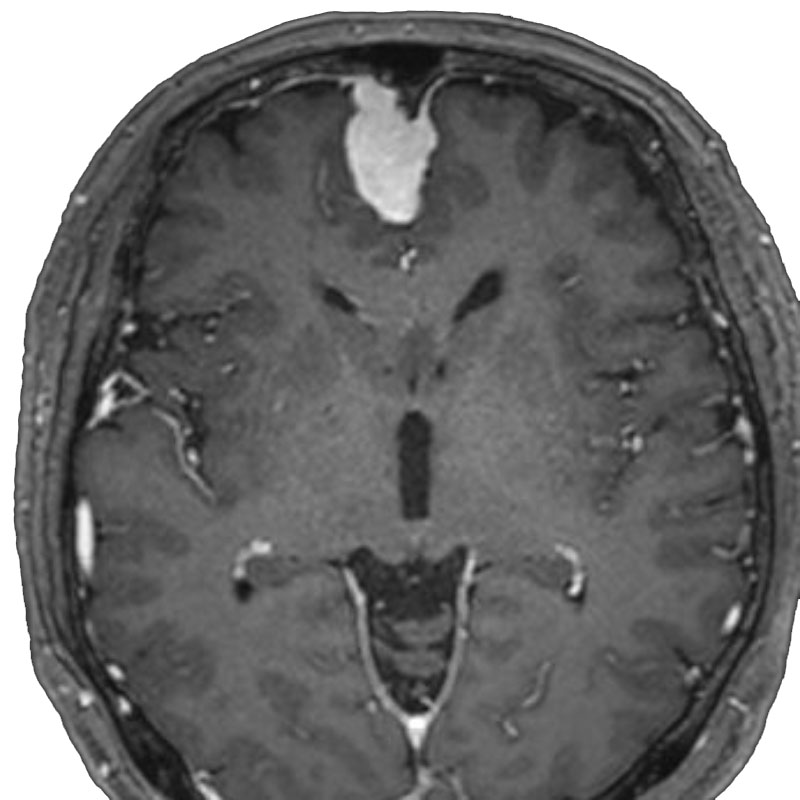

脳動脈瘤(Acom)

クリッピング術

松田/濵田/元永